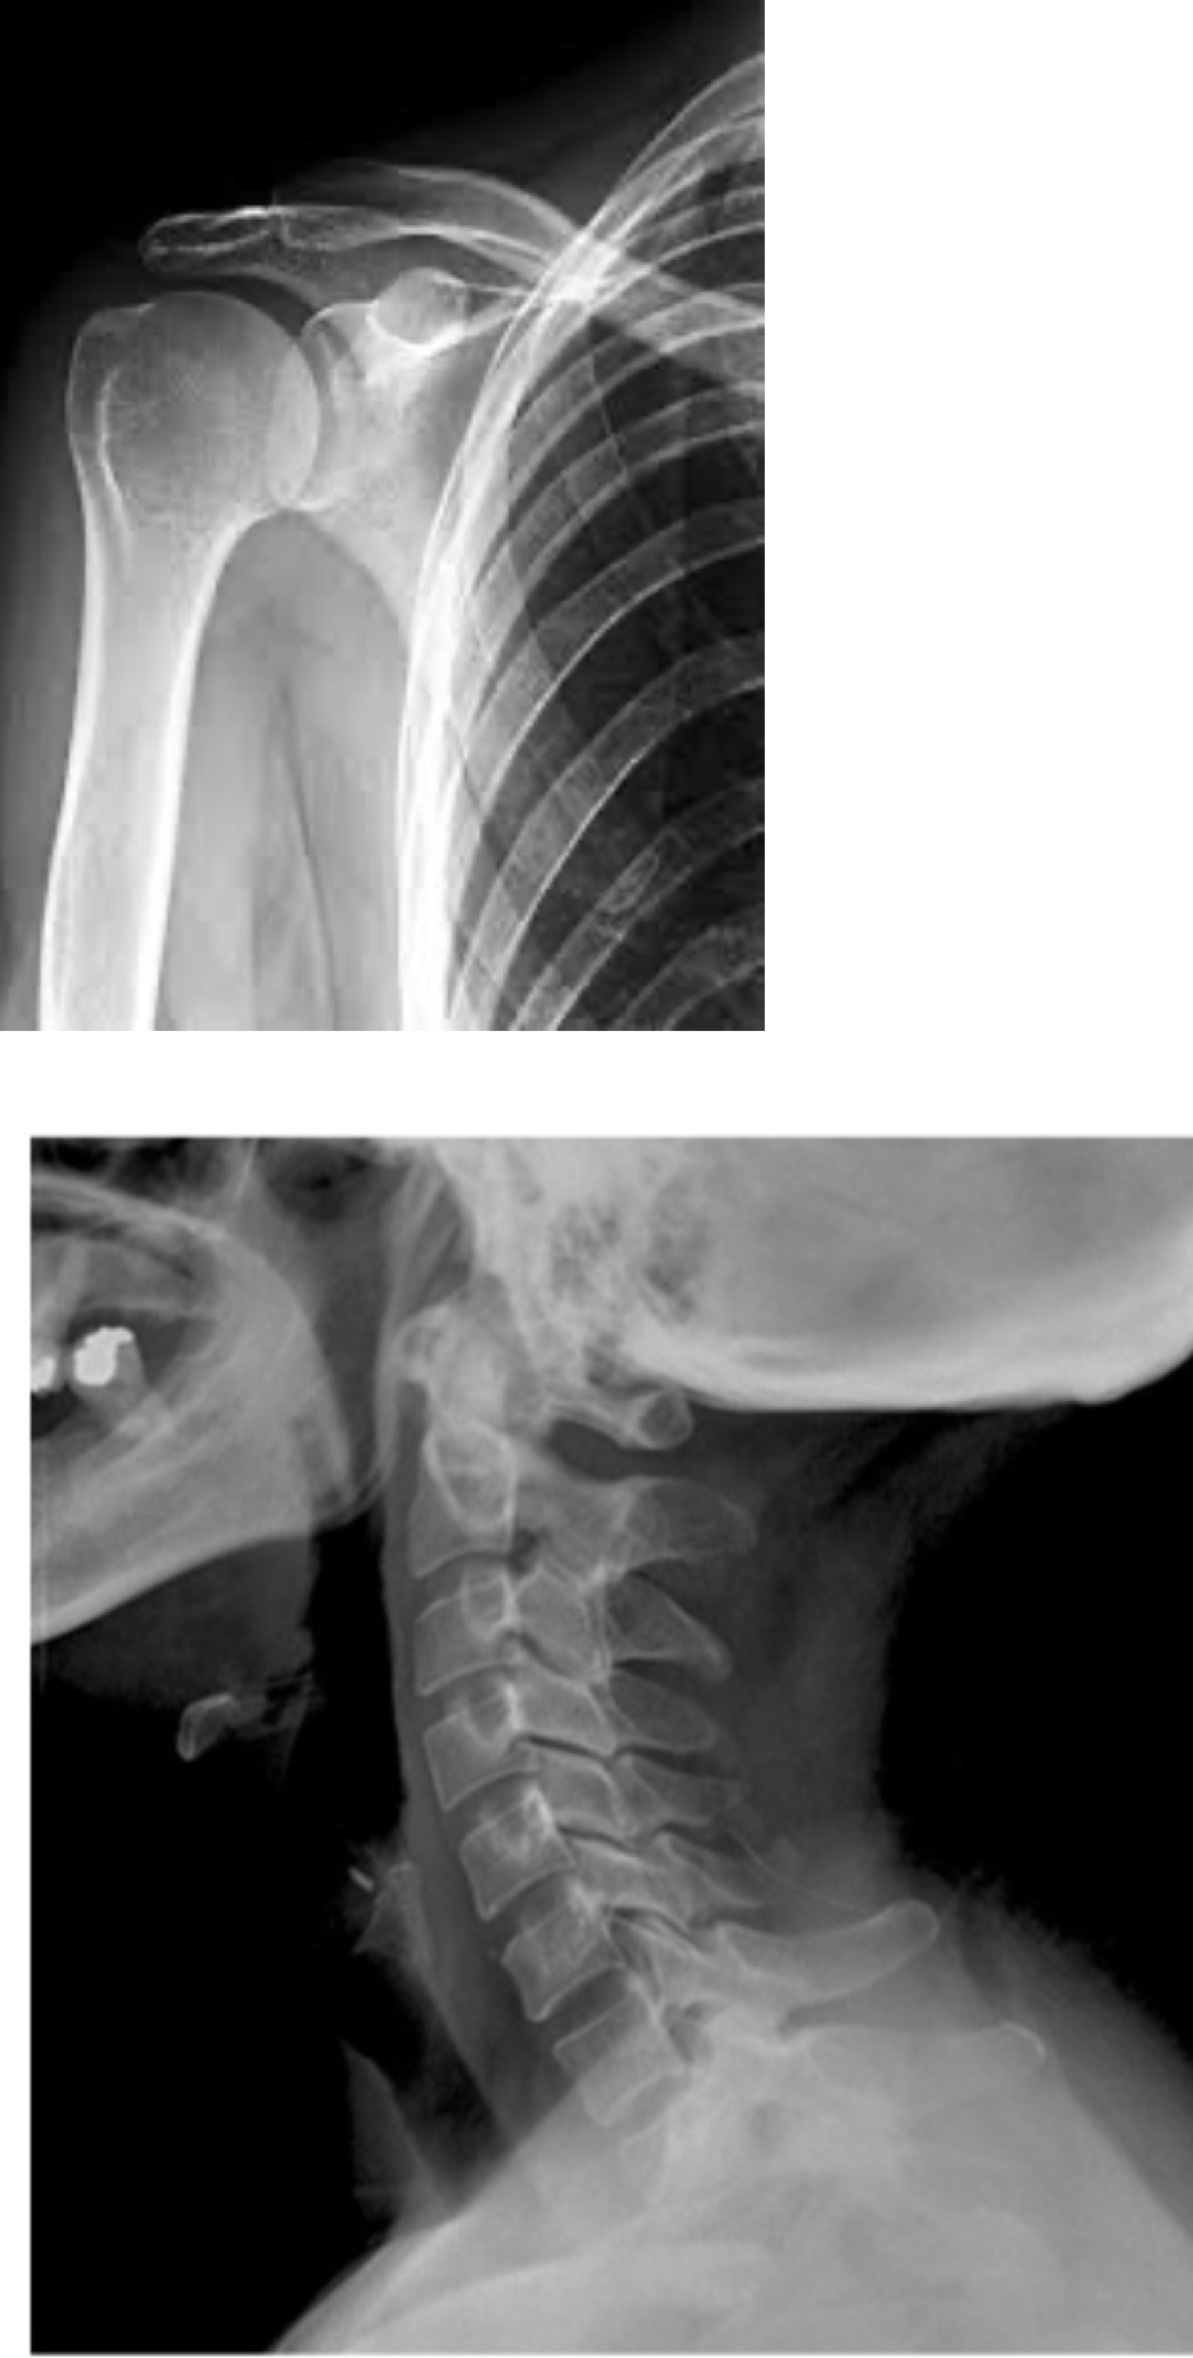

Masculino de 41 años de edad, oficinista, practica halterofilia, manifiesta omalgia izquierda de 2 meses de evolución, irradiado hacia cuello, mano y dedos ipsilateral, entumecimiento de los 5 dedos, palidez de los mismos, mejora al elevar sus brazos por arriba de su cabeza. Cuenta con los siguientes estudios:

¿Cual es su sospecha diagnostica?

Pregunta 1 opciones:

Condroblastoma Humero Proximal

Neuritis Braquial

Síndrome del Túnel del Carpo

Síndrome de Salida Torácica

A